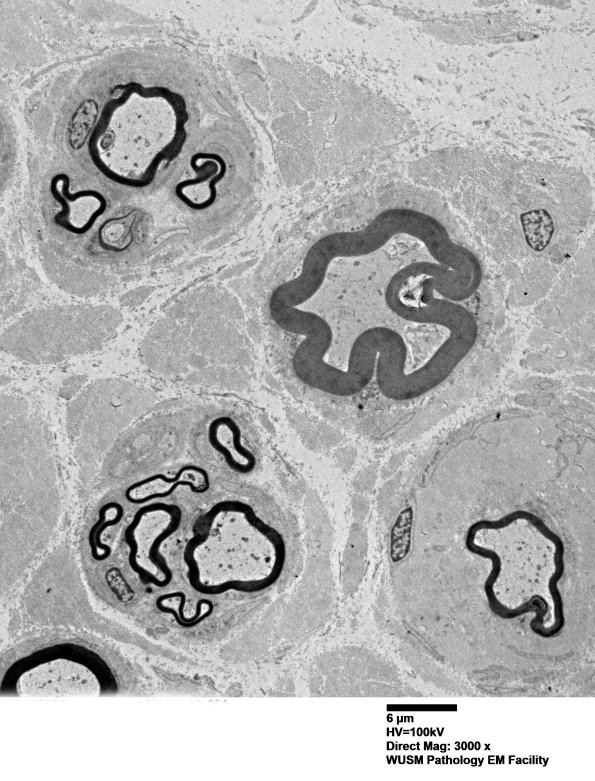

The axon density, presence of axons within clusters and axons with myelin which is too thin for axon caliber further suggest this is an abnormal biopsy.